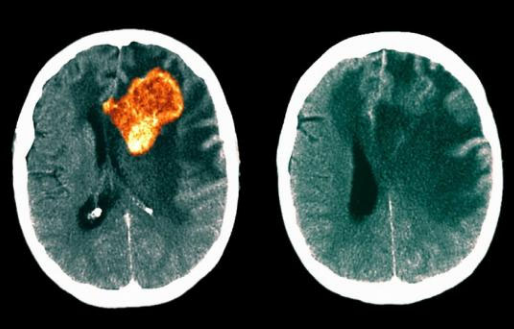

美国治疗胶质母细胞瘤 研制新抗原靶向疫苗